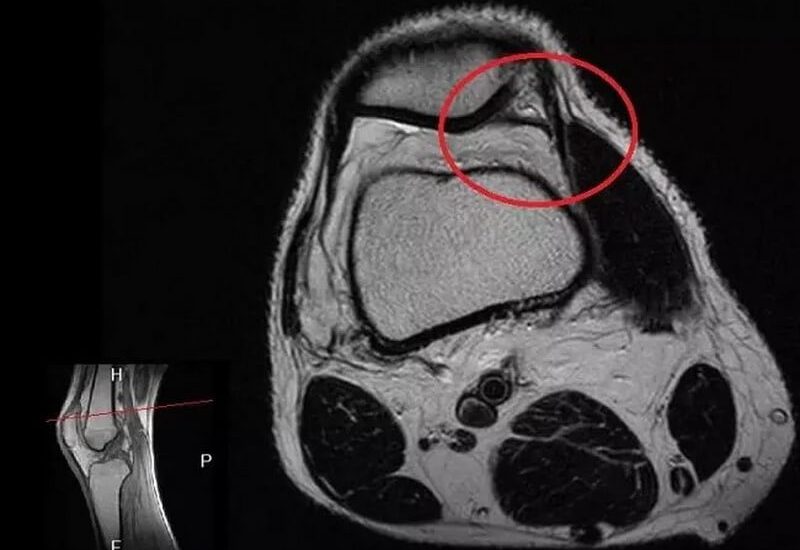

Артроскопічна резекція медіопателярної складки колінного суглоба (синдром медіопателярної складки, гіпертрофія медіопателярної складки) 1. Медіопателярна складка 2. Передня хрестоподібна складка 3. Верхній заворот колінного суглоба 4. Супрапателярна складка 5. Латеральна синовіальна складка 6. Інфрапателярна